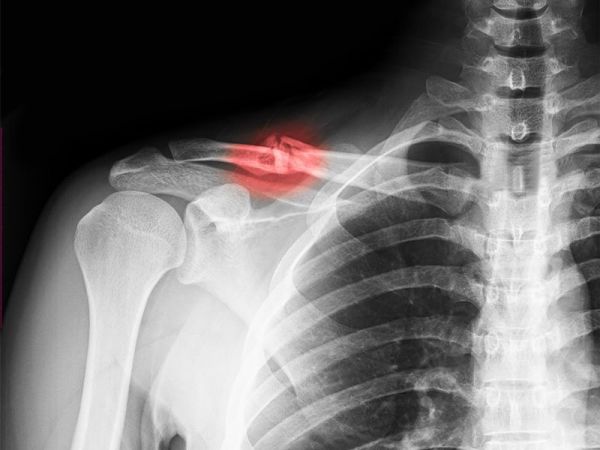

Las fracturas radiculares son una consecuencia relativamente rara de los traumatismos dentarios siendo su prevalencia alrededor de un 05-07 de entre todos los casos. Dente com raiz fraturada. Web retirada de um resto radicular.

Las fracturas pueden ser verticales horizontales o ligeramente oblicuas clasificándose según el tercio radicular donde se. Además estos pueden ir asociados a una clínica de necrosis pulpar o fracaso. São frequentemente descobertas quando o osso circundante se perde ou.